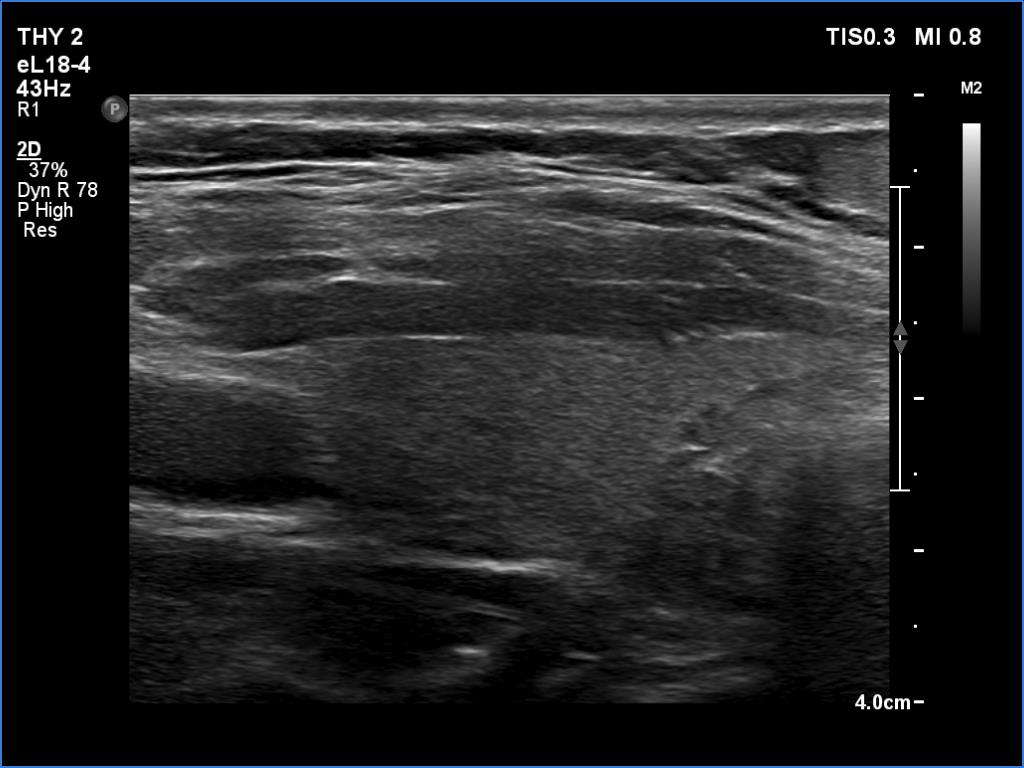

Ultrasonography. The thyroid was echonormal and had several small cystic lesions without any clinical or oncological importance. According to the palpable mass, a moderately hypoechoic lesion was detected several centimeters under the thyroid in the middle of the neck. The lesion was within the muscle tissue. It was homogeneous and presented no vascularity.